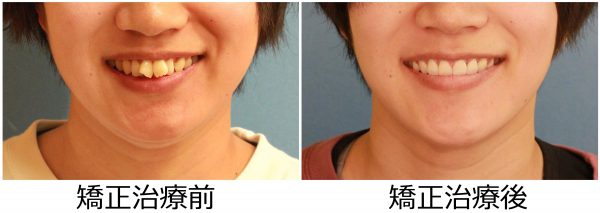

27歳 女性 「 ねじれ歯、出っ歯を治したい 」 ( 翼状捻転 )

「 ねじれ歯 と ”出っ歯” を治したい 」との事で来院されました。

とにかく「ねじれて ”出っ歯”な 前歯が目立つのが嫌だ」との事でした。

抜歯により、前歯の捻じれと 出っ歯感が解消しました。

前歯のねじれは改善し、大きく下がりました

前歯が大きく下がったことで、口もとの 印象が 大きく変わり

口もともスッキリと変化しました。

素敵な笑顔になりました! (#^.^#)

27歳 女性 叢生を伴う 上顎前突症 治療期間15か月 唇側矯正装置(ホワイトワイヤー)を使用した上下顎第一小臼歯抜歯治療 参考治療費 約65万円 (精密検査から終了まで) 矯正治療に伴う副作用の歯肉退縮、知覚過敏、失活、歯根吸収などは認められませんでした。